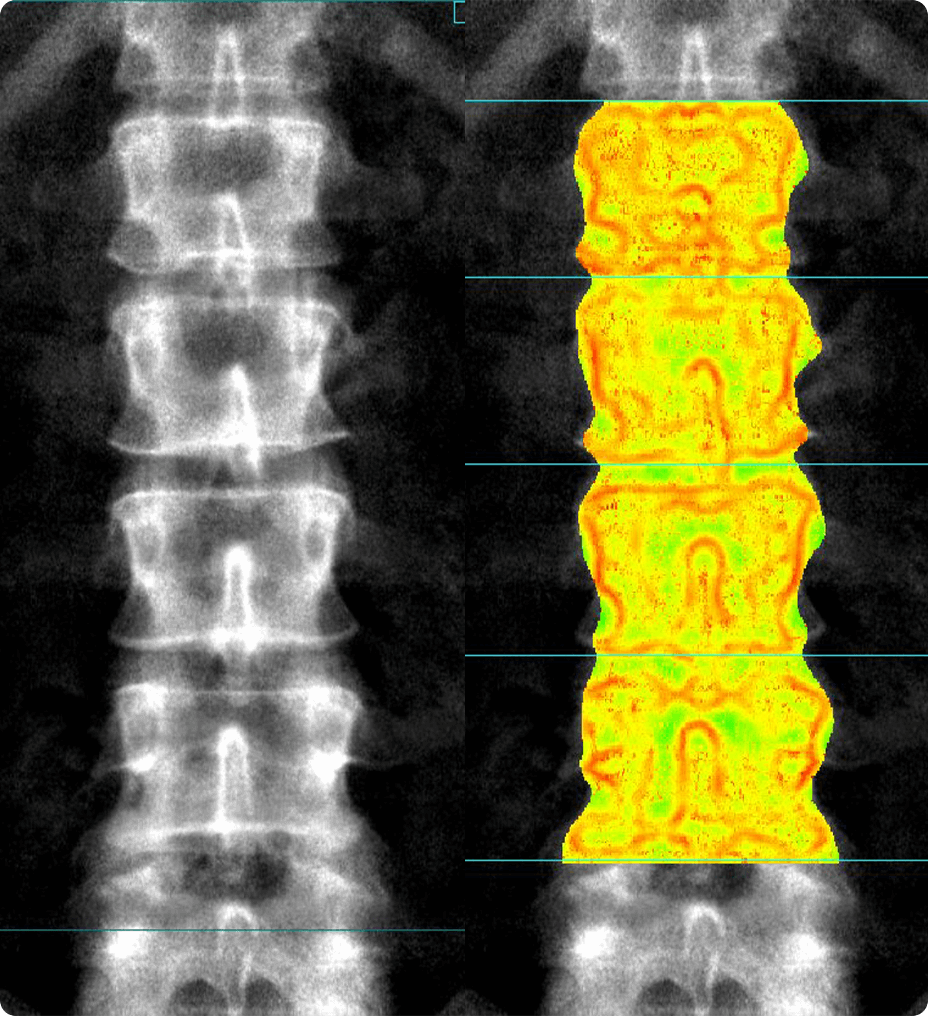

Nell’ambito oncologico, l’imaging di diffusione svolge un ruolo centrale. SIGNA™ Sprint permette di ottenere immagini più nitide, con una riduzione delle distorsioni e un SNR ottimizzato.¹

Il progressivo aumento delle esigenze diagnostiche in ambito oncologico e cardiologico richiede una risonanza magnetica capace di garantire qualità costante anche negli scenari più complessi. Con prestazioni del gradiente pari a 65/200, SIGNA™ Sprint offre immagini estremamente nitide e contribuisce a migliorare la sicurezza diagnostica. Il miglioramento del rapporto segnale‑rumore (SNR), l’evoluzione delle applicazioni di diffusione e l’impiego di soluzioni basate su deep learning ampliano le capacità diagnostiche e permettono di monitorare in modo più accurato la risposta terapeutica nei pazienti oncologici.¹